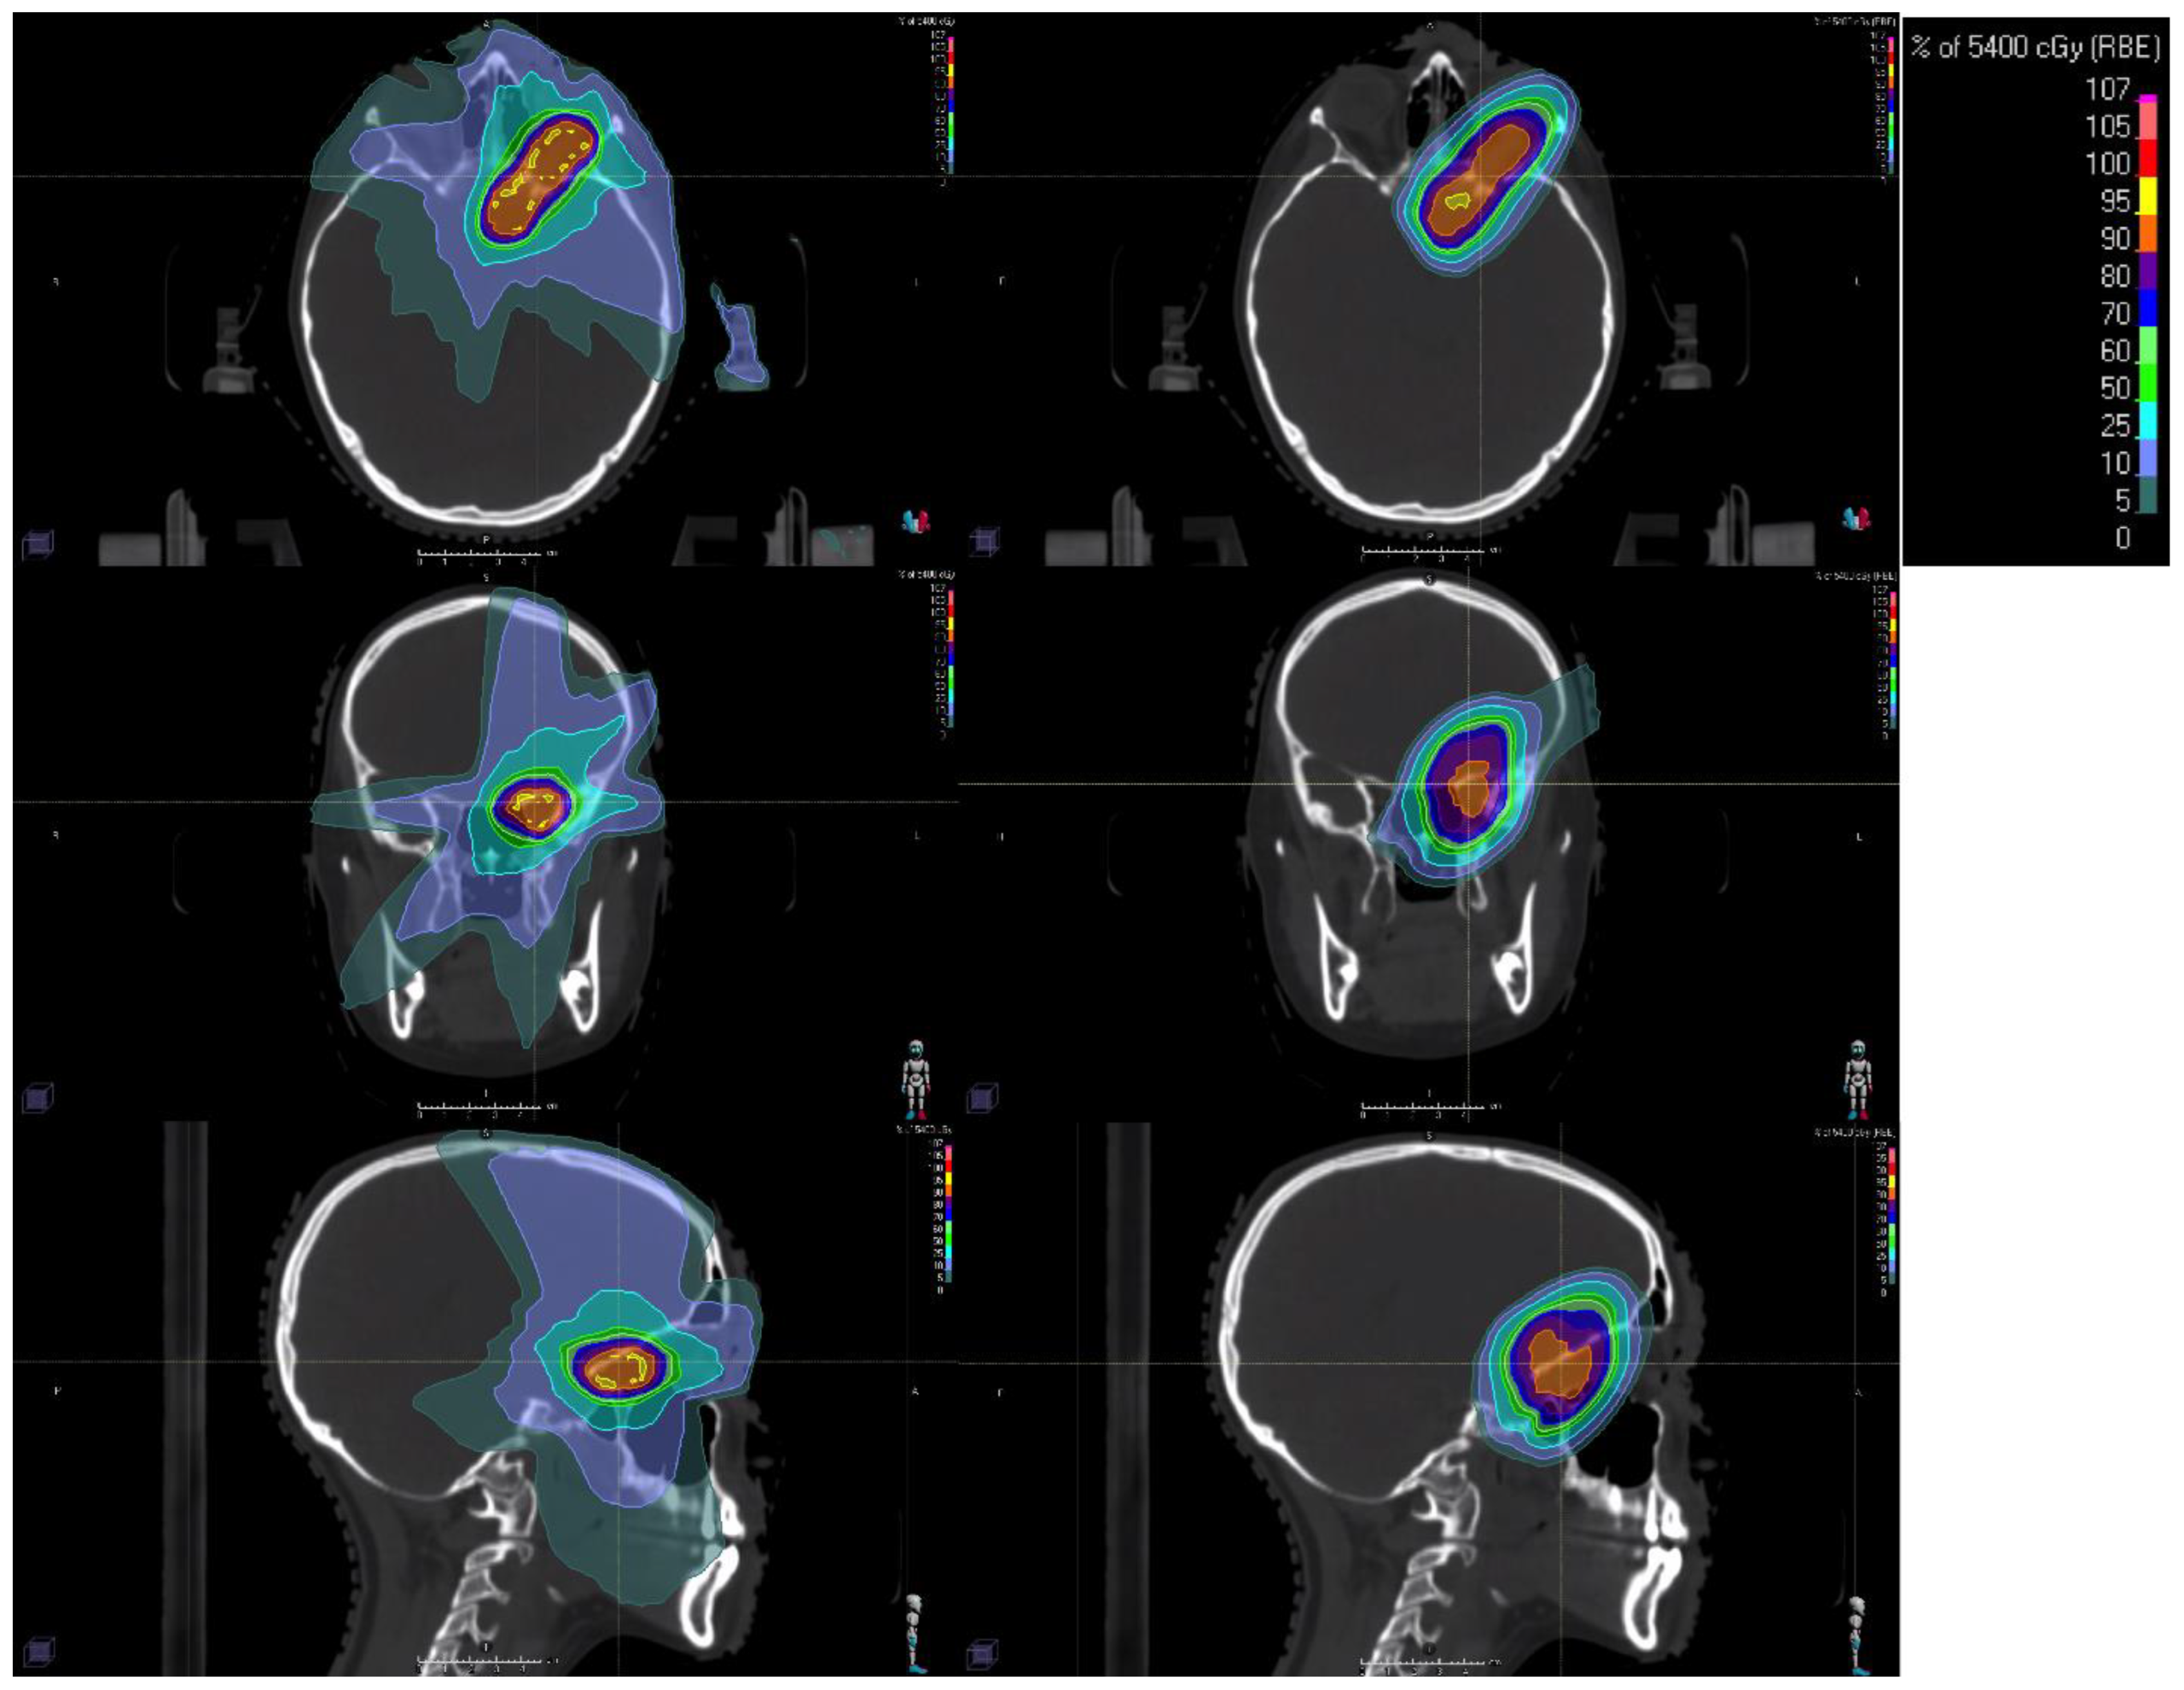

2. Proton Therapy

2.1. Planning and Delivery of Proton Therapy

| Intensity-Modulated Proton Therapy (IMPT) | A form of proton therapy that modulates the radiation dose to better conform to the tumor shape |

| Proton Beam Therapy (PBT) | A form of radiation therapy that uses protons instead of photons to deliver targeted radiation, reducing damage to surrounding normal tissues |